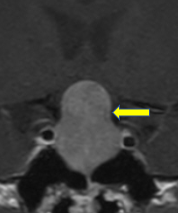

66歳男性 腰椎椎間板ヘルニア(上行性)

腰椎全体の変形があり、腰部脊柱管狭窄症の診断で、他院で治療を受けられていました。

右足の痛みが強く歩行に支障があるため相談にみえられました。2/3腰椎右に椎間板が上方に逸脱して、神経が強く圧迫されていましたので、手術を行いました。

全体に問題がありますが、神経に最も負担になっている部分のみを手術すると負担も少なく、効果的です。